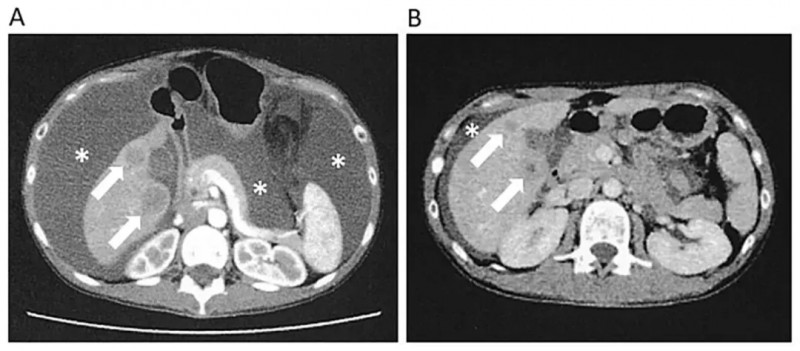

1、腹水与指标变化:治疗前患者存在大量腹水,治疗期间腹水逐步减少,至第56天腹水明显减少且肝转移灶同步缩小(详见下图),印证NK细胞疗法对控制腹膜播散效果显著。此外,第三次NK细胞治疗后,患者癌胚抗原(CEA)、糖类抗原125(CA125)水平明显下降,腹围也显著减小。

▲图源“Cureus”,版权归原作者所有,如无意中侵犯了知识产权,请联系我们删除